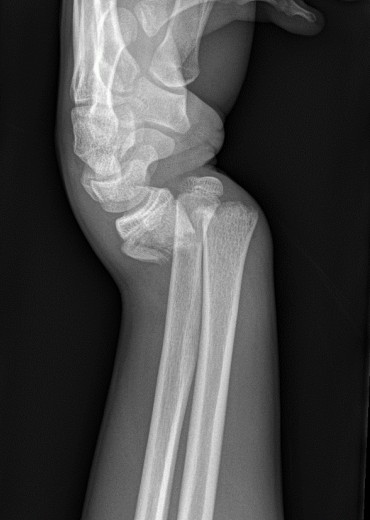

Wrist injury

A 38-year-old man presents with a painful left wrist after a fall on an outstretched hand. X-rays are provided.